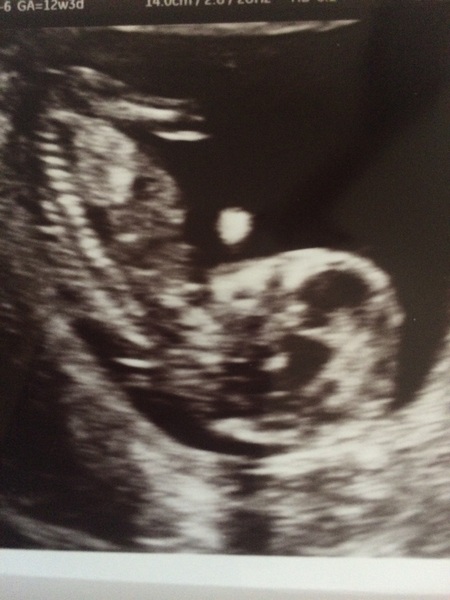

Flingmoo · 15/11/2016 13:22

Here's my picture! I think it's not clear enough for guesses on gender?! It is waving its hand nicely though Grin